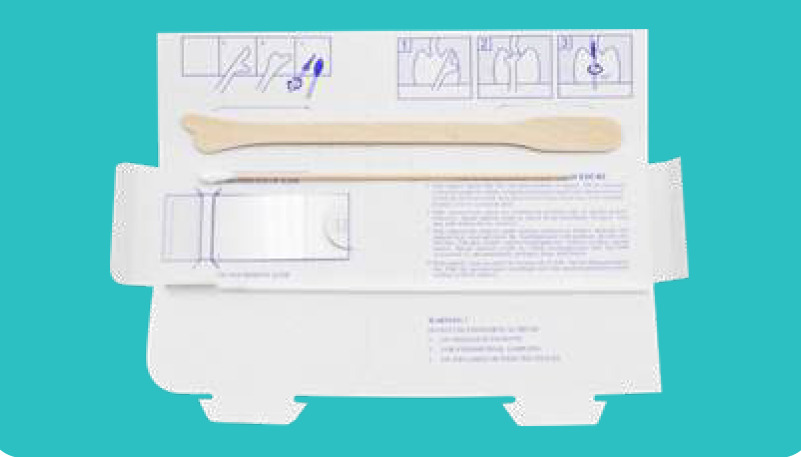

Disposable PAP Smear Kit

Content: 1pc X Wooden Cervical scraper, 1pc X Cervical brush

1pc X Slide glass, 1pc X Cotton tipped applicators

Packing: 1set/paper box/Blister bag, 400sets/ ctn 57.5x43x22cm